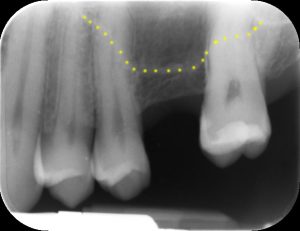

| Inadeguata quantità di osso residuo per inserire un impianto. | Con la tecnica del mini-rialzo l’impianto è stato inserito contemporaneamente al piccolo innesto di osso. |

| in giallo evidenziato il contorno della base del seno mascellare | in giallo evidenziata la porzione di osso innestato |